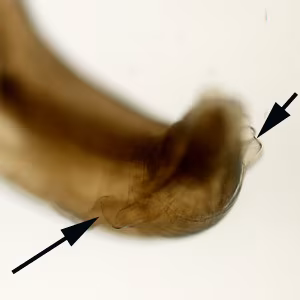

A state public health laboratory received three worms from a regional commercial laboratory for identification. The public health laboratory submitted the worms to the CDC/DPDx Team for diagnostic assistance. The submission form indicated that how and where the worms were collected was not provided by the commercial laboratory. Figure A shows all three worms for gross presentation and size determination. A dissecting microscope was used to observe morphologic features. Figures A and B shows two separate focal planes of the anterior of one worm; Figures C, D and E show three aspects of the tail. What is your diagnosis? Based on what morphologic features.

Figure C